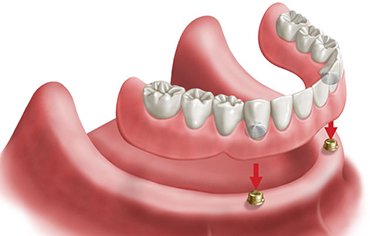

In case of completely missing teeth implant supported DENTURES can give better retention and stability and hence chewing efficiency is more.